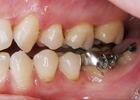

虫歯、歯周病の問題を解決した上で矯正治療を行い、

矯正治療終了後、矯正治療では不可能な微妙なかみ合わせの調整をして、

全身とかみ合わせのバランスを整えます。(→かみ合わせ治療) |

・健康な歯

・健康な歯肉(歯周組織)

・全身とのバランスがとれたかみ合わせ(→かみ合わせ治療) |

| この3つがすべてそろうことで矯正治療は成立します。 |